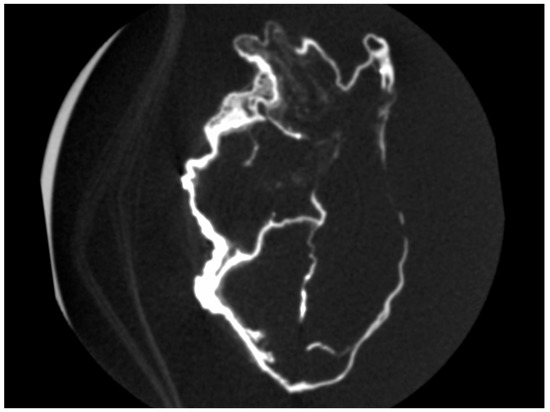

2.2. Micro-CT Scan

4.2. Micro-CT Scan